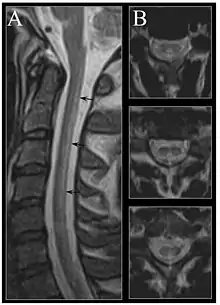

Image of the cervical spinal cord in vitamin B12 deficiency showing subacute combined degeneration. (A) The midsagittal T2 weighted image shows linear hyperintensity in the posterior portion of the cervical tract of the spinal cord (black arrows). (B) Axial T2 weighted images reveal the selective involvement of the posterior columns. | |

MRI of the brain may show periventricular white matter abnormalities. MRI of the spinal cord may show linear hyperintensity in the posterior portion of the cervical tract of the spinal cord, with selective involvement of the posterior columns.